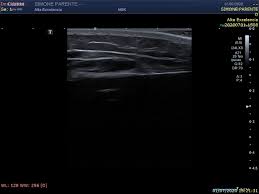

- 젤을 바른 후 초음파 탐촉자를 경동맥 위에 대고 영상 관찰

- 혈류 속도 측정과 플라크 유무 확인

- 검사 시간: 보통 10~20분 내외